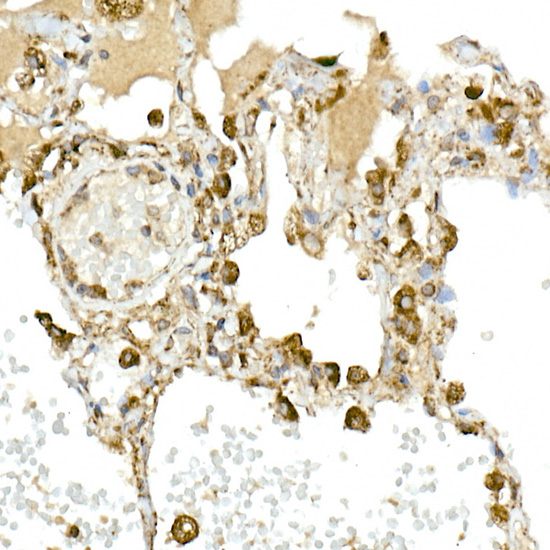

Immunohistochemistry of paraffin-embedded human lung using MMP14/MT1-MMP Rabbit pAb.